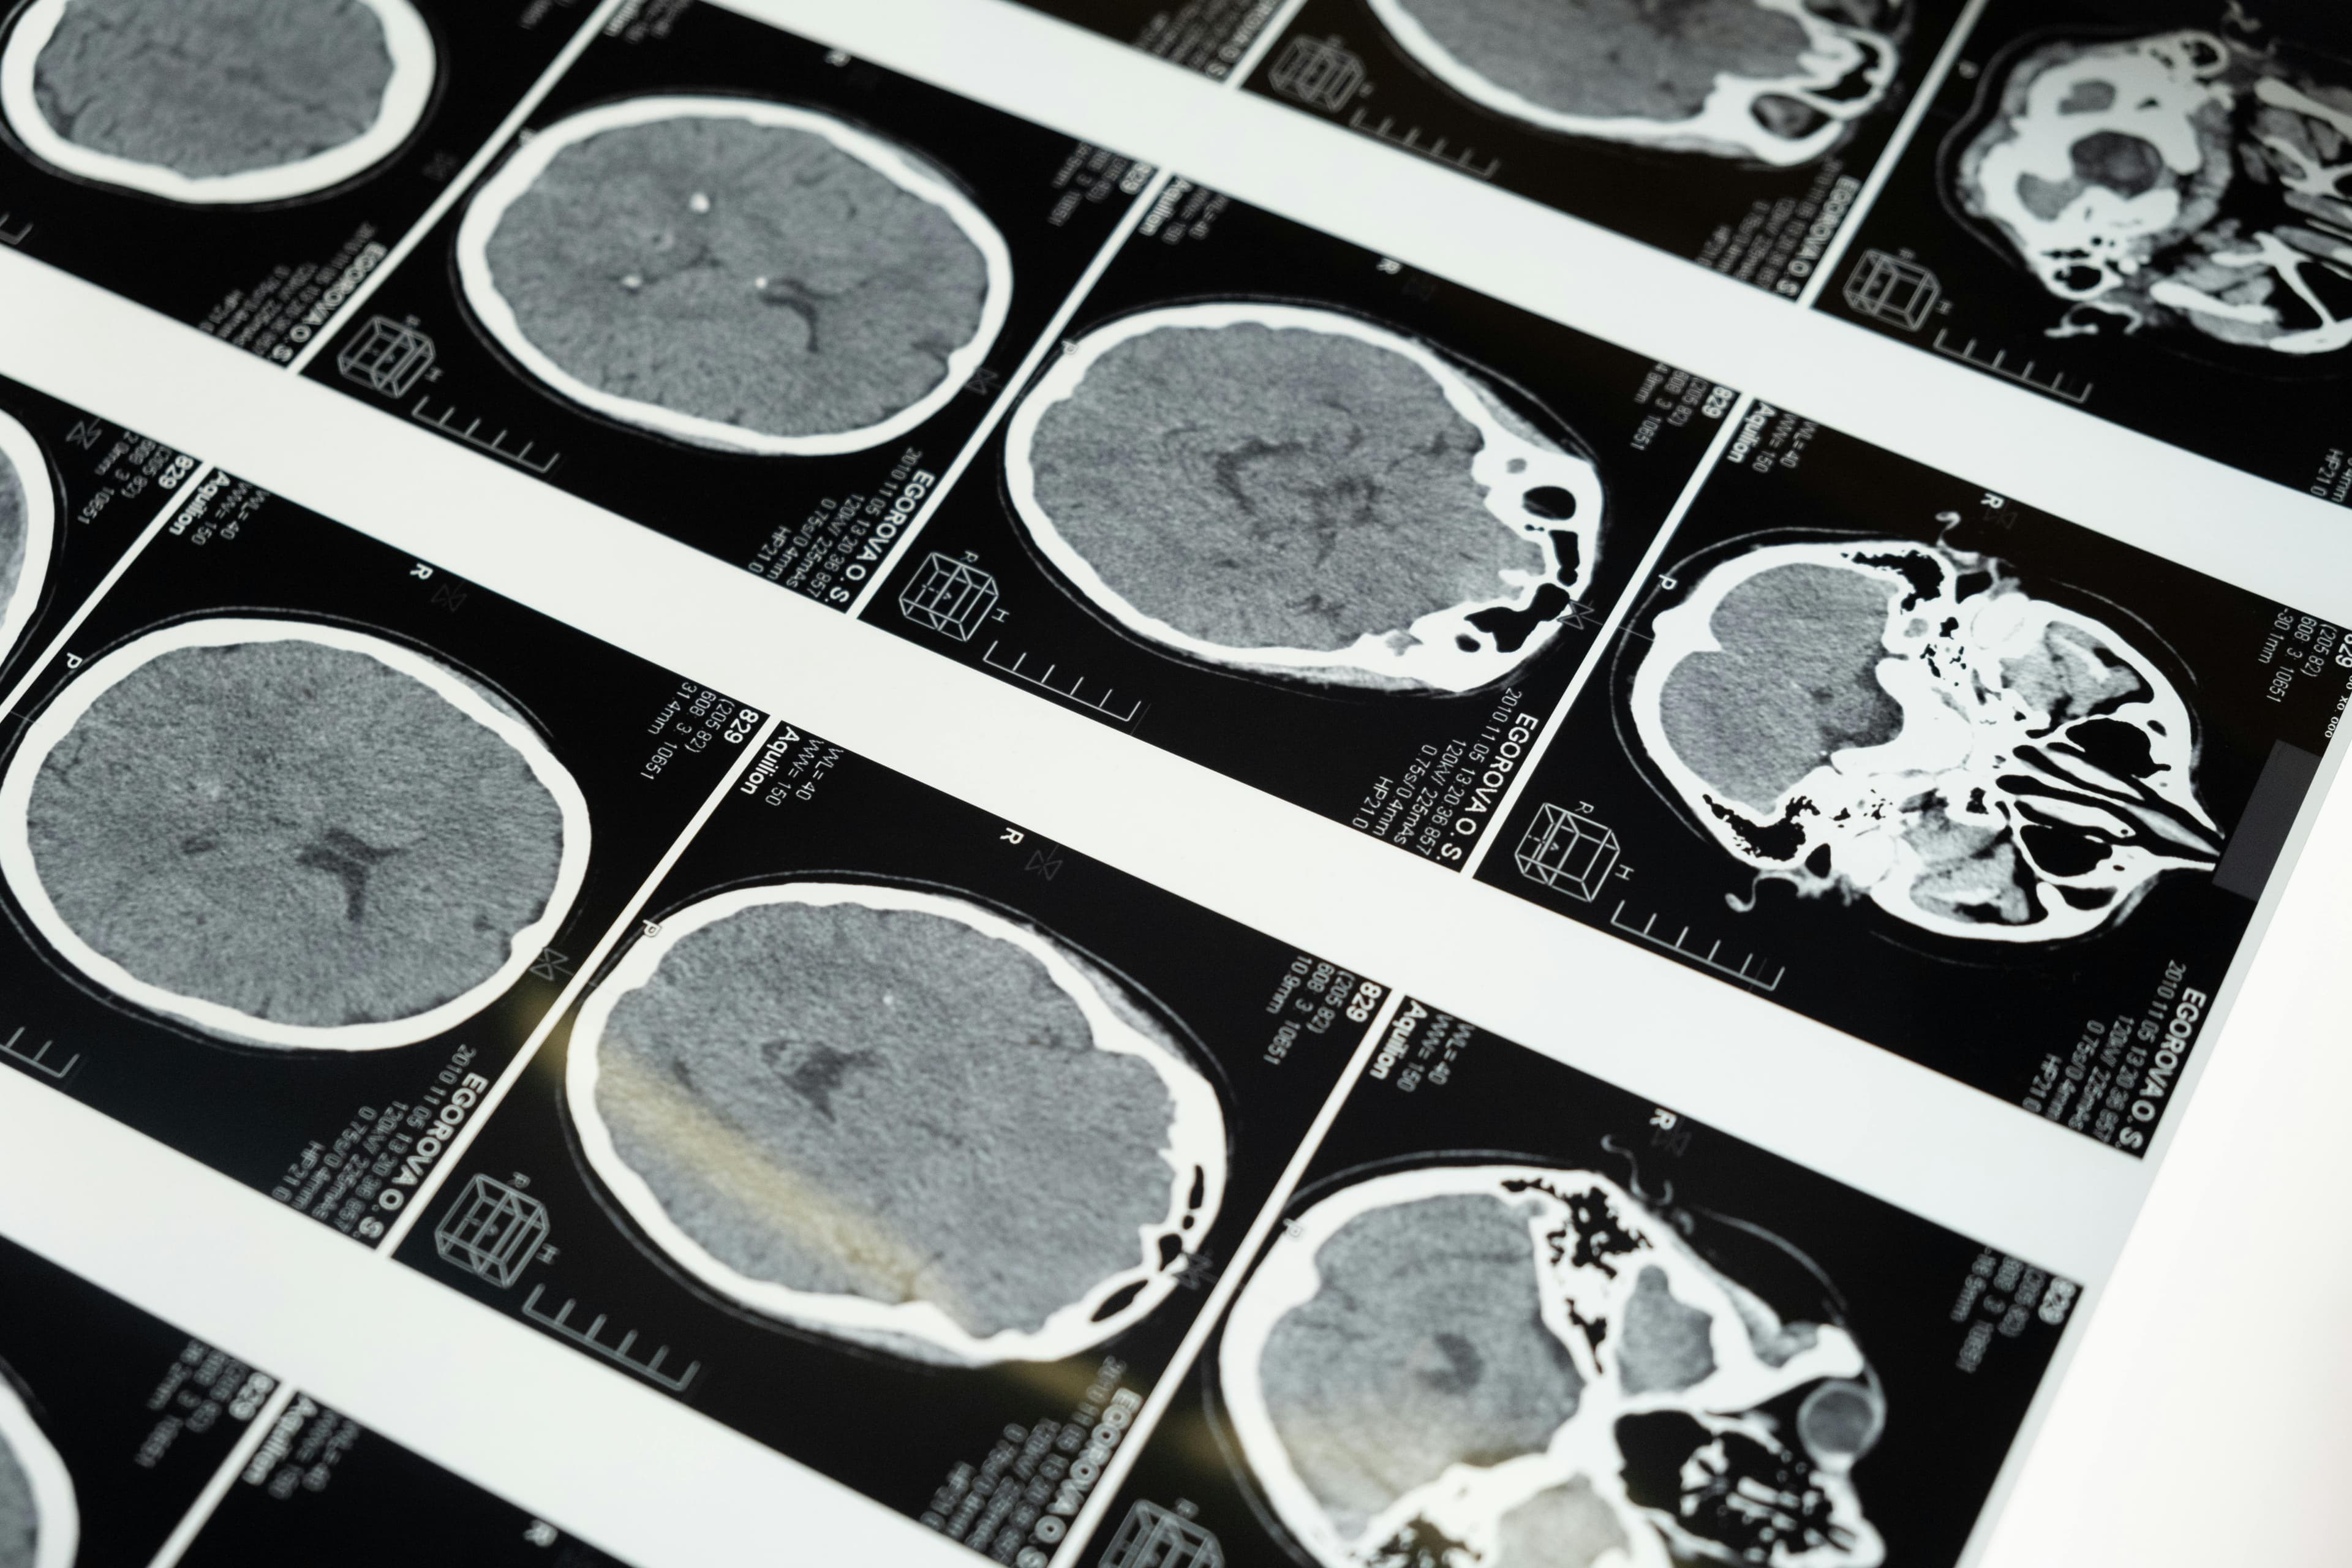

This article explains acquired brain injury, its causes, symptoms, and the role of MRI in diagnosis, highlighting Brain Mapping Solutions' advanced imaging technology.

Acquired brain injury (ABI) refers to any brain damage that occurs after birth and is not related to congenital or degenerative diseases. ABI can result from various causes, including traumatic brain injuries, strokes, infections, and lack of oxygen to the brain. Diagnosing ABI accurately is crucial for effective treatment and rehabilitation. At Brain Mapping Solutions, we use advanced MRI technology to diagnose and monitor ABI, providing detailed images that help in understanding the extent and impact of the injury.

The Role of MRI in Diagnosing ABI

MRI is a powerful tool in diagnosing ABI as it provides high-resolution images of brain structures. At Brain Mapping Solutions, our MRI scans can detect:

- Brain tissue damage

- Swelling and inflammation

- Hemorrhages and blood clots

- Structural abnormalities

- Changes in brain activity

How Brain Mapping Solutions Utilizes MRI Technology

Our advanced MRI technology at Brain Mapping Solutions allows us to create detailed maps of the brain, highlighting areas affected by ABI. This detailed imaging is crucial for brain injury specialists to develop effective care plans and rehabilitation strategies for patients.